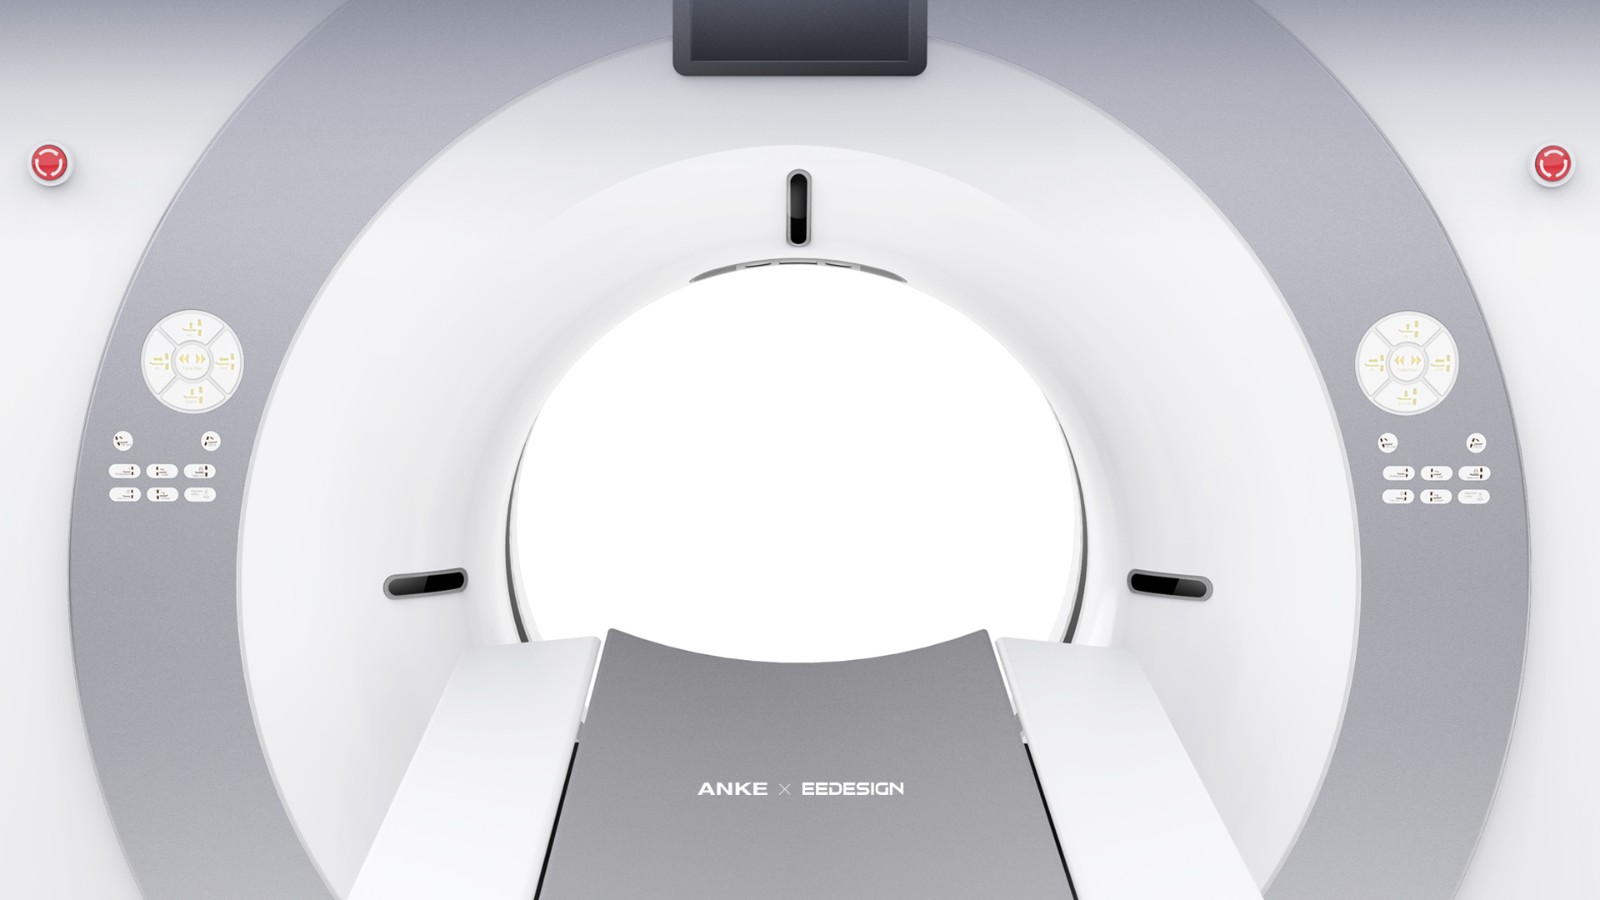

深圳市(shì)東(dōng)象設計(jì)有(yǒu)限公司,成立于2017年(nián)

專注為(wèi)全球醫(yī)療企業(yè)提供具有(yǒu)價值的(de)工(gōng)業(yè)設計(jì)解決方案,團隊核心成員(®yuán)均有(yǒu)15年(nián)以上(shàng)醫(yī)療器(qì)械研發設計(jì)經驗,榮獲包←含世界三大(dà)設計(jì)獎(reddot、IF、IDEA)在內(nèi)的(de)近(jìn)百餘知( zhī)名設計(jì)獎項,是(shì)醫(yī)療行(xíng)業(yè)發展速度較快(kuài)的(de)設計(jì)公司

專注為(wèi)全球醫(yī)療企業(yè)提供具有(yǒu)價值的(de)工(gōng)業(yè)設計(jì)解決方案,團隊核心成員(®yuán)均有(yǒu)15年(nián)以上(shàng)醫(yī)療器(qì)械研發設計(jì)經驗,榮獲包←含世界三大(dà)設計(jì)獎(reddot、IF、IDEA)在內(nèi)的(de)近(jìn)百餘知( zhī)名設計(jì)獎項,是(shì)醫(yī)療行(xíng)業(yè)發展速度較快(kuài)的(de)設計(jì)公司